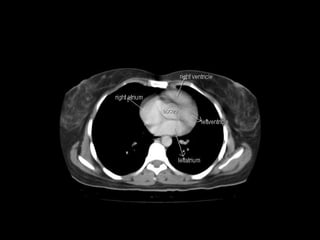

Radiographers use medical imaging equipment like X-rays and MRIs to produce images of patients' internal structures and organs. They are responsible for positioning patients, operating scanning machines, and ensuring quality images. Radiographers must have strong attention to detail, excellent communication skills, and the ability to work well under pressure to accurately capture anatomical features and diagnose any abnormalities.